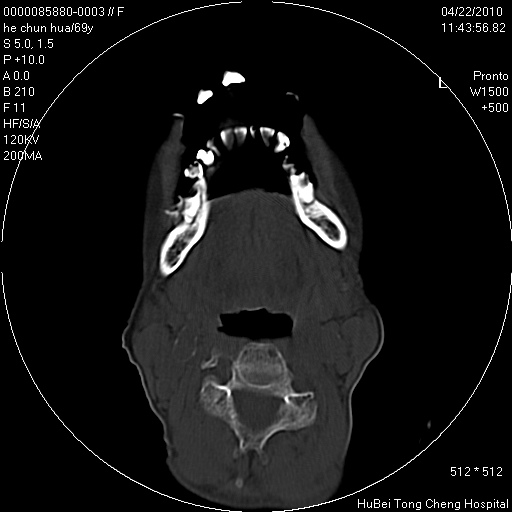

标题: CT25937:女,69Y

硬腭部包块十余年,渐进性增大。

病程长,考虑巨细胞修复性肉芽肿可能性大;

鉴别:神经源性病变、硬结病等。

五楼说得有道理,支持一下。巨细胞修复性肉芽肿好象是外伤出血后引起的修复性改变,骨质呈溶骨性破坏,但病程呈良性过程。

考虑硬腭部肿瘤恶变,gcrg可能,鉴别于gct。